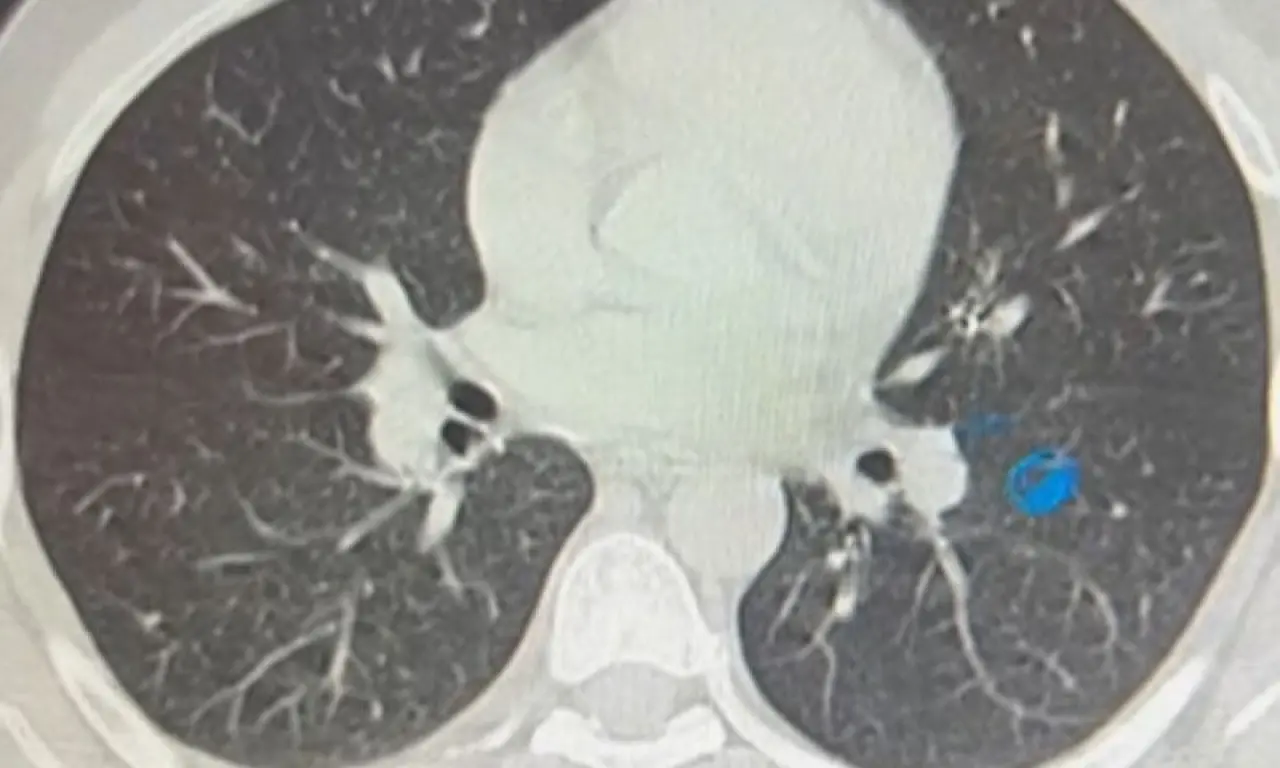

İmplant vidası, yapılan ilk kontrollerde hastanın sol akciğerinde, bronşların derin bir bölümüne saplanmış halde bulundu. Solunumu tamamen engellemeyen bu durum, yine de müdahale gerektirecek düzeyde tehlikeliydi.